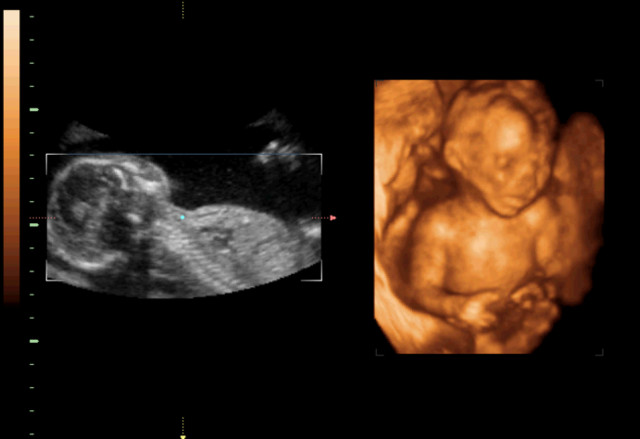

30岁的小孙就有唇裂,修补过的疤痕仍很分明。在最近一次三维B超显示,腹中的胎儿居然中度唇裂。她通知大夫,因为她诞生就有唇裂,小时老是被讪笑和厌弃。所有,无论怎样也要流掉腹中的宝宝,她不想让她的孩子再经历这样的经历。

大夫却通知小孙,现在已经孕21周,如果引产对身材损伤十分大,如果在次怀孕,不能包证就不会得唇腭裂,第二次仍会怀上唇腭裂宝宝的几率约为4%,假如怀过两次唇腭裂的宝宝,第三次怀上唇腭裂宝宝的几率会提升到14%。如今婴儿唇腭裂整形手艺,已经十分胜利,即使是重度的唇腭裂,仍是能够修补得简直看不出来了。倡议把孩子生上去,不要因为这点瑕疵,就将宝宝的性命闭幕。